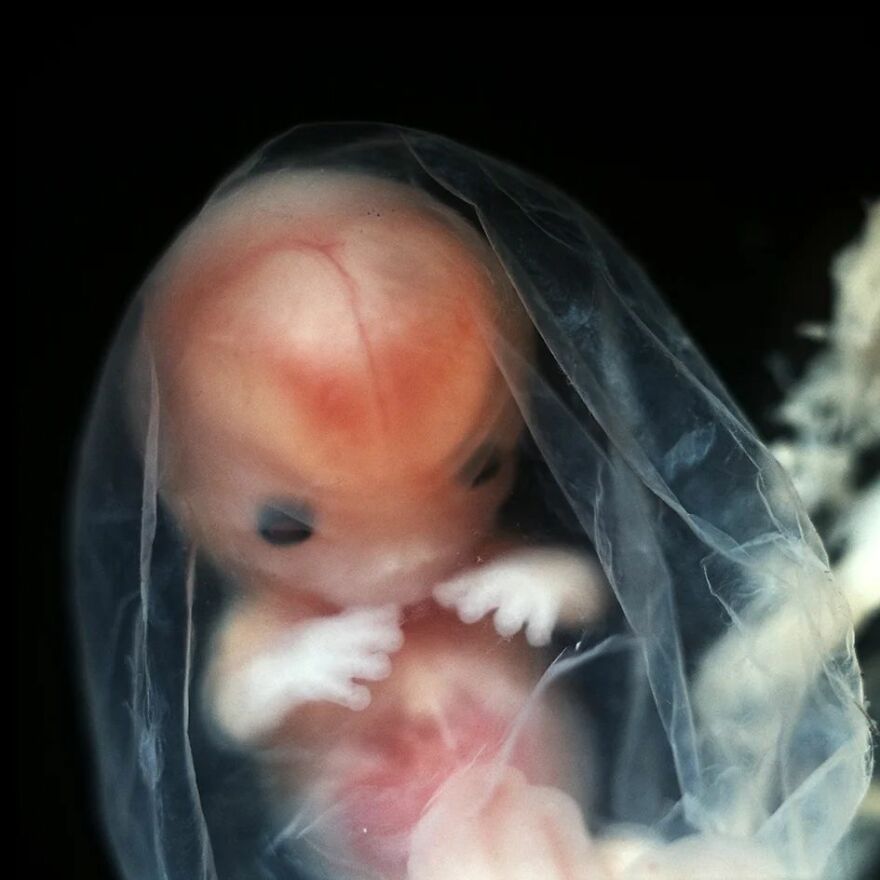

Development of the hand, week 8

From the book "A Child is Born", 2003